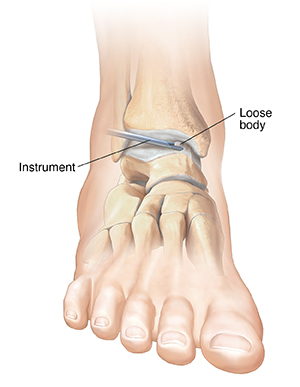

Loose bodies

Loose bodies are bone or cartilage fragments that have chipped off inside the joint. If left in place, they can damage the joint surface, cause pain, and restrict ankle movement. Your surgeon can remove loose bodies from the joint. This will help restore normal, smooth ankle motion.